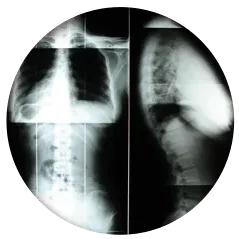

- Full Spine X-rays: Comprehensive imaging to identify spinal misalignments and guide personalized treatment plans.